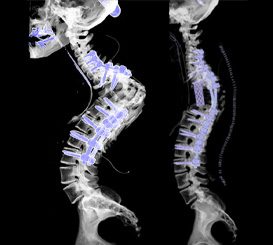

Dr. Yash Shah is one of the very few National Board certified, Degree [FNB(Spine)] honored Spine specialist is recognized amongst the best spine surgeons of our country. He heads the Mumbai Spine Clinic, a premium health care provider for patients suffering from Back Pain, neck pain, Spondylosis, Slip disc, Disc herniation, Spinal Stenosis, Spine TB, Scoliosis and Kyphosis or spine deformity.

A Conservative(non-surgical) treatment is tried initially for most patients as most of our patients improve with the same. Surgery is offered when absolutely indicated and proven to give better results and are done with latest technologies at some of the best hospitals in Mumbai with well- equipped operation theatres.

Comparing Endoscopic Spine Surgery to Traditional Open Surgery: Which Is Right for You?

Recovery After Endoscopic Spine Surgery: What to Expect and How to Prepare

Understanding Endoscopic Spine Surgery: A Minimally Invasive Solution for Back Pain